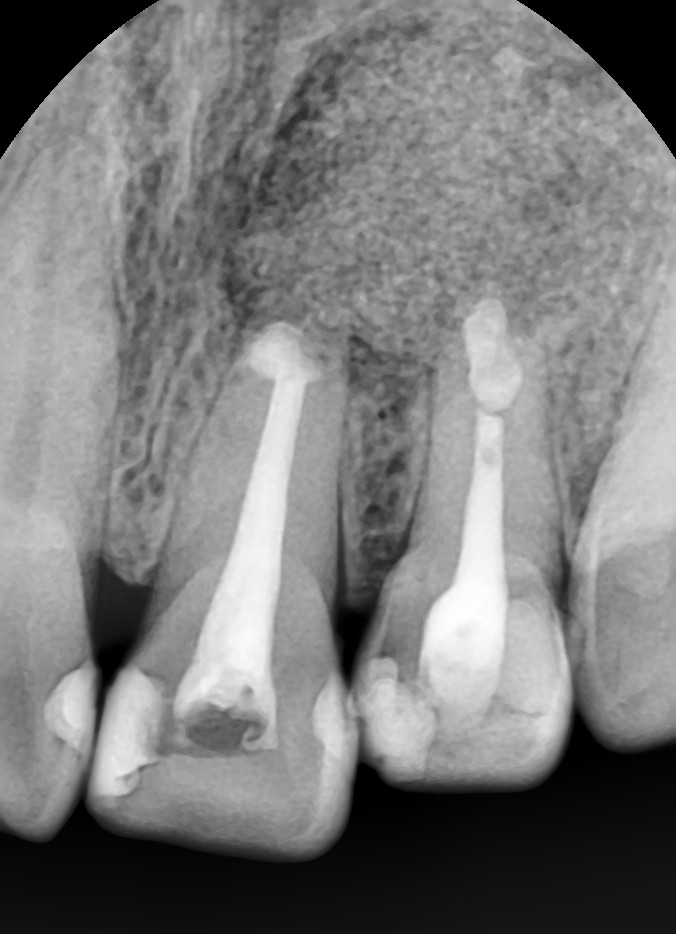

2013-06-19 초진pano#21,22

초진 내원시 찍은 환자분의 방사선사진입니다.  왼쪽 위 중절치와 측절치에 치근 아래에 동그란 모양의 잇몸뼈가 차있지 않는 것을 알 수 있습니다.

2013-06-19 초진 #21,22

작은 사진을 찍어 보았습니다. 중절치는 예전에 신경치료를 받으셨고 측절치는 신경치료가 되어 있지 않았습니다. 그리고 두 치아 사이가 어두운 색으로 보이는 부분이 있는데  이로써 잇몸뼈가 차있지 않음을 다시 확인할 수 있었습니다. 일단 먼저 측절치의 신경치료를 진행하면서 예후를 관찰해 보기로 하였습니다.  그런데 신경치료 후에도 염증의 사이즈가 줄어들지 않아서 치근단수술을 진행하기로 하였습니다.